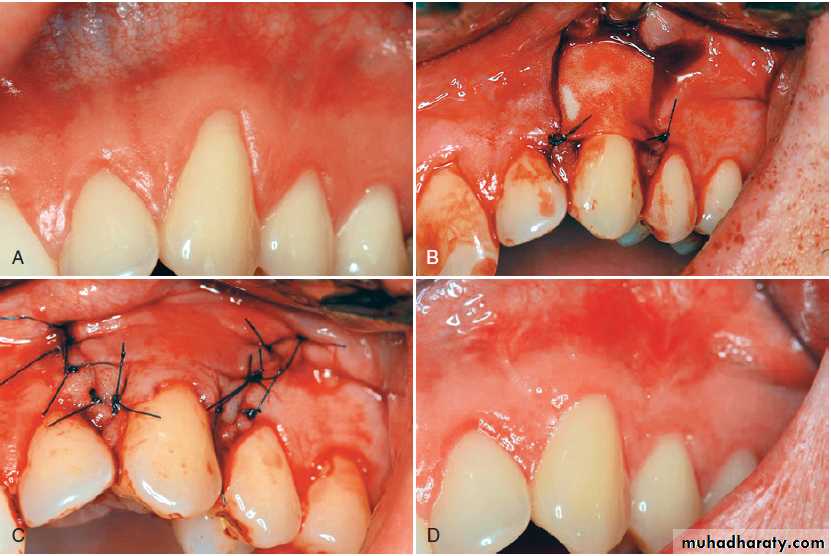

Frenectomy is complete removal of the frenum, including its attachment to underlying bone, and it may be required in the correction of an abnormal diastema between the maxillary central incisors.

Frenotomy is relocation of the frenum, usually in a more apical position.

Removal of the frenum. (A) Preoperative view of frenum between the two maxillary central incisors. (B) Removal of the frenum from the lip and gingiva. (C) The site is sutured after a connective tissue graft is placed over the wound. (D) Postoperative view at 2 weeks.